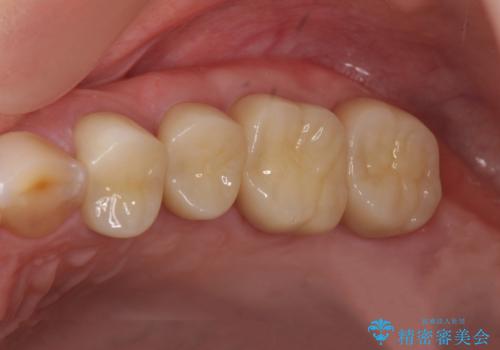

虫歯の深化により根管治療、歯周外科手術を行い歯肉の状態を改善し精密なセラミッククラウンを製作する治療を計画します。

- 50万円(仮歯・ファイバーコア・ジルコニアクラウン×4 歯周外科)費用は治療当時の料金となります

セラミック治療の長期的な予後を見込むために、根管治療、歯周外科を行いクラウン装着前の環境を整えておくことが肝要です。